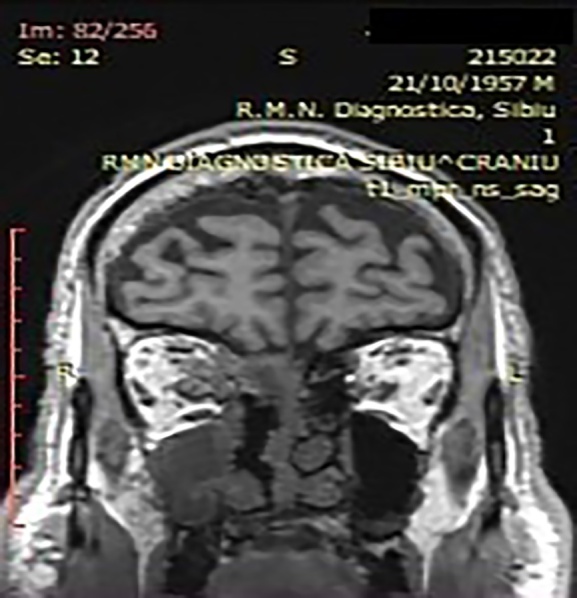

犀牛毒素粘孢子菌病是一种急性侵袭性真菌感染,临床上很少见,多发于严重免疫抑制的患者。然而,在 COVID-19 疾病患者中,粘孢子菌病的发病率急剧上升。本研究旨在讨论 COVID-19 相关粘孢子菌病患者的磁共振成像结果。本研究对 2021 年 2 月 1 日至 2021 年 10 月 30 日期间在三个耳鼻喉科住院和手术的 10 名患者进行了回顾性研究。所有患者均患有鼻腔粘液瘤病,经组织学验证,SARS-CoV-2 RT-PCR 检测呈阳性。所有患者均有鼻窦受累、鼻窦外扩散和鼻窦周围侵犯的记录。磁共振成像与术中发现之间的相关性也得到了评估。黑鼻甲征和鼻甲周围软组织浸润是粘液瘤病的早期磁共振特征。此外,磁共振成像对 COVID-19 相关粘液瘤病的术中发现具有很高的阳性预测价值。

Rhino-sinusal mucormycosis is an acute invasive fungal infection rarely encountered in the clinical setting, occurring in severe immunosuppressed patients. However, in patients suffering from COVID-19 disease a dramatic increase in the incidence of mucormycosis has been recorded. The aim of the study is to discuss the MRI findings of patients with COVID-19 associated mucormycosis. This is a retrospective review of 10 hospitalized and operated patients in three Otolaryngologic Departments between the 1st of February 2021 and the 30th of October 2021. All patients presented nasal mucormycosis, histologically verified along with documented SARS-CoV-2 positive RT-PCR test. The sinus involvement, extra sinus spread and peri-sinus invasion were documented in all patients. The correlation between MRI and intra-operative findings was also assessed. The black turbinate sign and peri-antral soft tissue infiltration are early MRI signs characteristic of mucormycosis. Moreoever, MRI has a significantly high positive predictive value for intra-operative findings in COVID-19 associated mucormycosis.